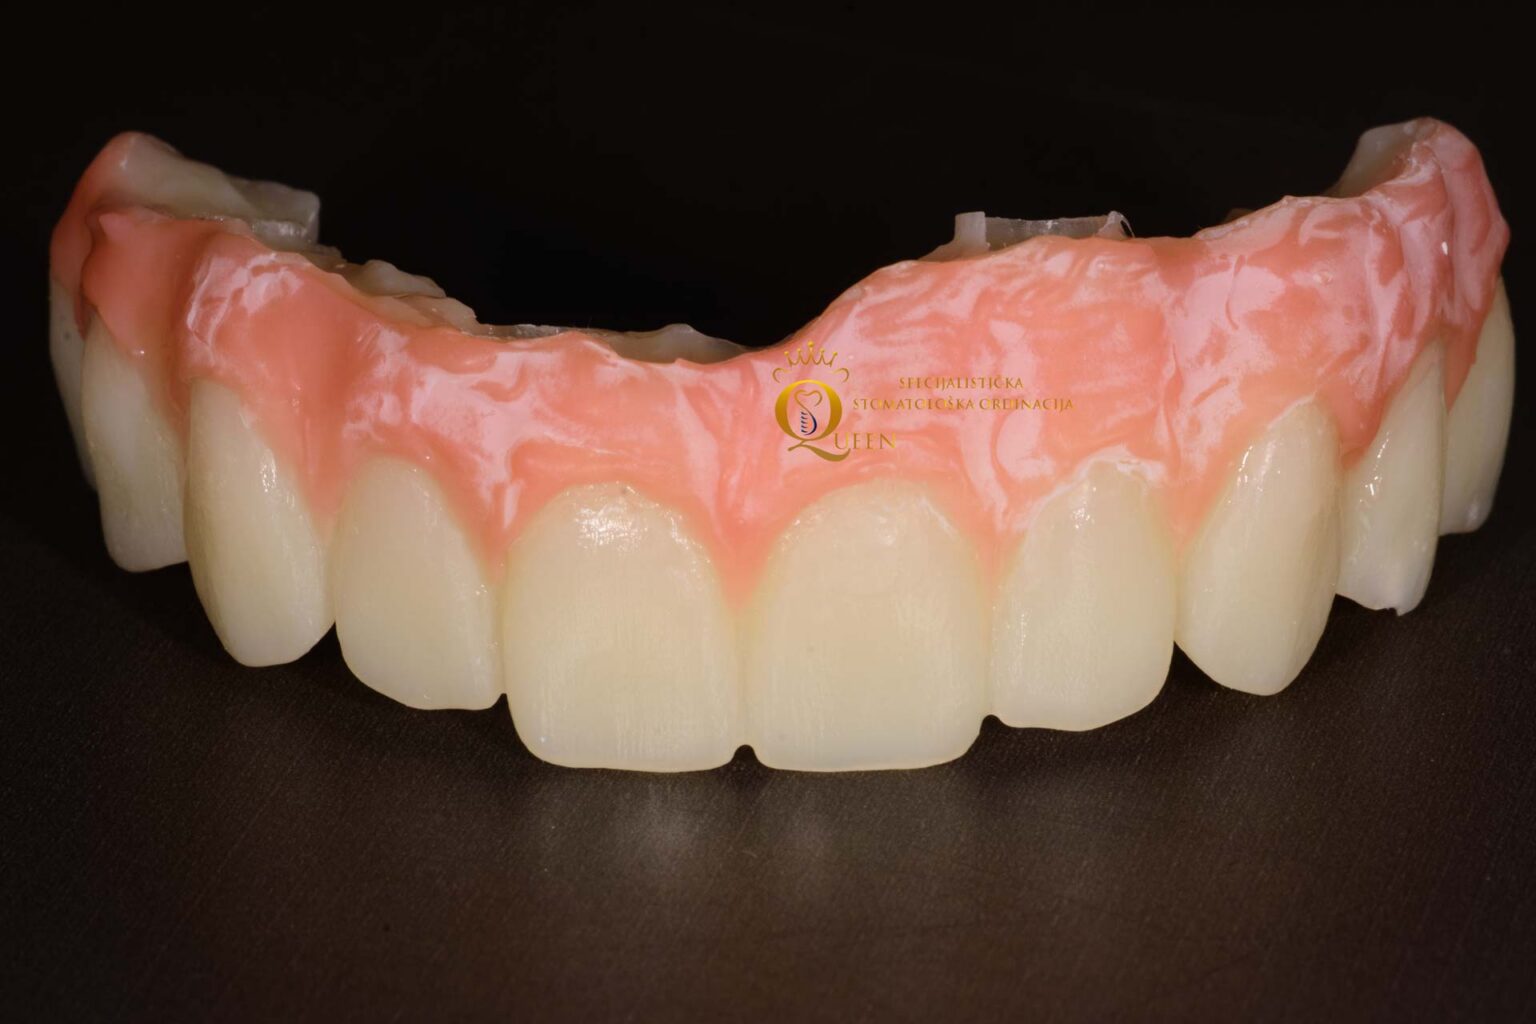

Here you can see how the temporary teeth look like.

This is also one final ceramic bridge, so you can see how it can look like.

All on four implants are very appreciative from an aesthetic point of view. You can practically have a Hollywood smile or imitate your natural teeth from your younger days. It consists of a white part (teeth) and a pink part that imitates the gums. It is characterized by complete harmony and harmony between the

“gingiva and teeth”.